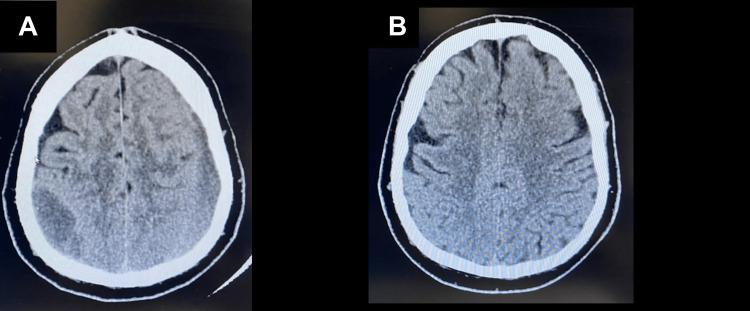

Epidural hematomas (EDHs) are a neurosurgical emergency characterized by the accumulation of blood in the epidural space surrounding the dura mater. Spontaneous resolution of EDH is an exceptionally rare occurrence, with only 16 cases reported in the medical literature where resolution occurred within 24 hours of onset. In this case report, we present a unique instance of a chronic EDH that spontaneously resolved over a period of seven months. This case adds to the scientific literature by highlighting an extremely prolonged duration of spontaneous EDH resolution, which, to our knowledge, has not been previously documented. A 59-year-old male suffered a head injury following a fall. He presented with a progressively worsening headache and nausea, raising concerns for a potential EDH. A computed tomography (CT) scan confirmed the presence of a large right parietal EDH measuring 58 × 23 × ​​​​​​​17 mm and a large left frontoparietal EDH measuring 90 × 20 ×​​​​​​​ 12 mm. These findings were crucial in establishing the primary diagnosis and guiding subsequent interventions. Upon diagnosis of the EDHs, the patient received conservative treatment and was closely monitored. Over a period of seven months, follow-up imaging revealed complete resolution of both EDHs, with restoration of normal midline structures and ventricular sizes. Notably, this represents the longest duration of spontaneous EDH resolution reported in the literature. We attribute this uncommon outcome to the activation of endogenous fibrinolytic pathways, which are responsible for dissolving blood clots and hematomas. In addition, the formation of new collateral blood vessels around the hematoma may help facilitate its resolution. This case underscores the significance of early recognition and vigilant monitoring of EDH cases. While immediate surgical intervention remains essential in most instances, conservative management can be considered in select cases. Our report demonstrates the possibility of spontaneous resolution of EDHs over an extended period, emphasizing the importance of continued observation and appropriate management. By shedding light on this rare occurrence, this case report contributes to the limited existing literature on the topic, providing valuable insights and adding to our understanding of EDH management.

硬膜外血肿(EDH)是一种神经外科急症,其特征是硬脑膜周围硬膜外间隙积血。EDH自发消退极为罕见,医学文献中仅报道过16例在发病24小时内消退的病例。在本病例报告中,我们呈现了一例独特的慢性EDH,其在七个月的时间里自发消退。该病例通过突出自发EDH消退的极长时间,为科学文献增添了内容,据我们所知,此前尚无相关记录。一名59岁男性跌倒后头部受伤。他出现头痛和恶心症状且逐渐加重,引发了对可能存在EDH的担忧。计算机断层扫描(CT)证实存在一个58×23×17mm的巨大右侧顶叶EDH以及一个90×20×12mm的巨大左侧额顶叶EDH。这些发现对于确立初步诊断和指导后续干预至关重要。诊断出EDH后,患者接受了保守治疗并受到密切监测。在七个月的时间里,后续影像学检查显示两个EDH均完全消退,中线结构和脑室大小恢复正常。值得注意的是,这是文献中报道的自发EDH消退持续时间最长的案例。我们将这种不寻常的结果归因于内源性纤溶途径的激活,该途径负责溶解血凝块和血肿。此外,血肿周围新侧支血管的形成可能有助于促进其消退。本病例强调了早期识别和对EDH病例进行密切监测的重要性。虽然在大多数情况下立即进行手术干预仍然至关重要,但在某些特定病例中可以考虑保守治疗。我们的报告证明了EDH在较长时间内自发消退的可能性,强调了持续观察和适当管理的重要性。通过揭示这一罕见情况,本病例报告为该主题有限的现有文献做出了贡献,提供了有价值的见解并增进了我们对EDH管理的理解。